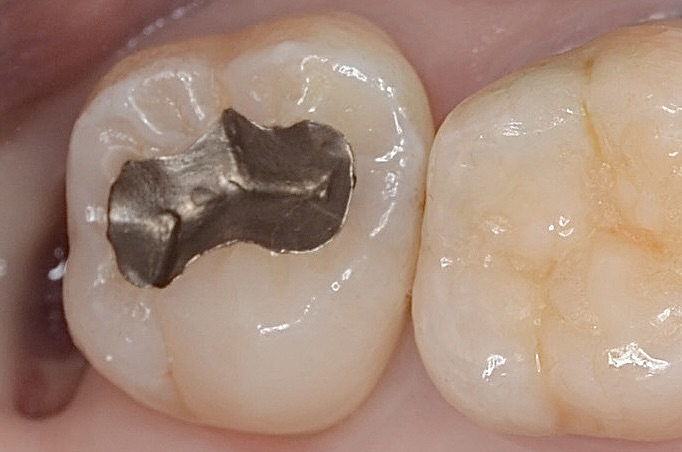

ラバーダム装着

7番のインレーを外します。 -

インレー

インレーの下の虫歯を除去します。 -